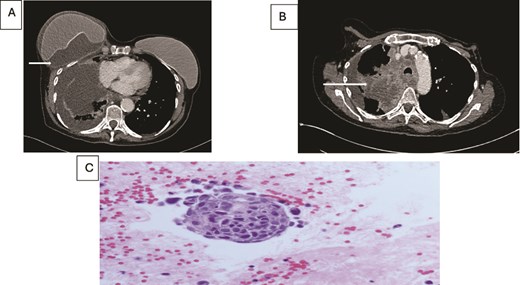

A 73-year-old female, ex-smoker, with a history of bilateral breast cancer and delayed implant-based breast reconstruction (14 years and 10 years prior, respectively) presented with new swelling in the right breast. Clinical assessment, followed by ultrasound, revealed no evidence of implant rupture but identified a large seroma. The seroma was aspirated, and the fluid was sent for cytological analysis to exclude BIA-ALCL. The cytology report returned as inflammatory fluid.

Concurrently she was being investigated for cough and weight loss with a CT scan which noted a right-sided pleural effusion and further fluid accumulation around the breast implant, as well as a right upper lobe lung lesion (Fig. 2). A biopsy of the lung lesion confirmed a poorly differentiated squamous cell carcinoma and further aspirations of the persistent right breast peri-prosthetic effusion revealed metastatic malignant cells consistent with a primary lung origin.

(A) Axial contrast enhanced CT scan shows heterogeneous lung mass with mediastinal invasion. (B) Axial CT image showing peri-implant malignant effusion. (C) fluid around breast implant: groups of atypical cells with hyperchromatic nuclei, high nuclear: cytoplasmic ratio and prominent nucleoli. The appearances are similar to the lung carcinoma diagnosed.